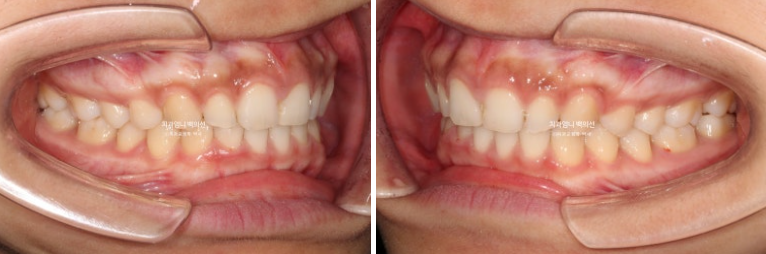

24.03~25.01

좋아진 배열과 사라진 틈.

과개교합의 확실한 개선

앞니가 뒤로 쓰러져 있던 옥니도 상당히 개선되었습니다.